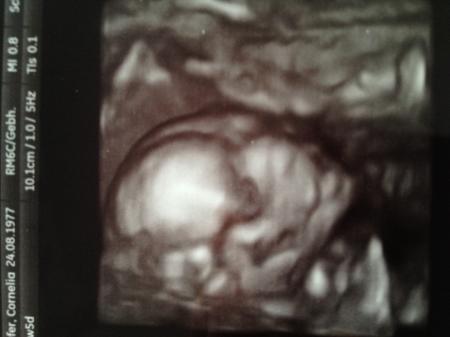

Hi Ihr Lieben! Vielen Dank für das Daumen drücken! Unsere Maus ist 19,88 cm groß und scheint einen Schmollmund zu haben Organe sind alle in Ordnung, arbeitet alles schon fleißig, Kiefer-Gaumen-Spalte sieht auch super aus. Eine kleine Turnerin wirds wohl, die Füße waren teilweise über dem Kopf Ach ja, es bleibt beim Mädel! Sie lag in Beckenendlage und ich hab eine Vorderwandplazenta. Ist das gut? Hatte zwar nachgefragt, hab ihn aber nicht verstanden...

Hier noch das Bild